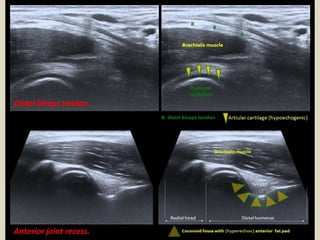

Distal biceps tendon.

Anterior joint recess.